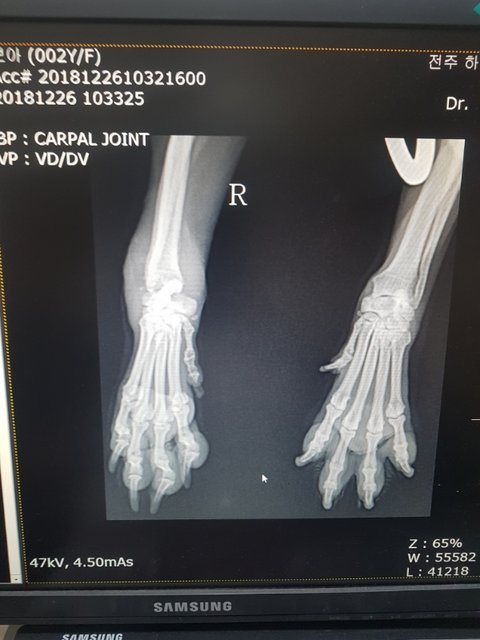

골절...염증이 심해 연골과 뼈일부분이 녹아내리고 있다고 합니다

염증먼저 가라앉히고 수술여부를 결정하신다고 합니다

2살추정 6.5키로 여아입니다